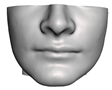

2.5.1. Bones

2.5.2. Soft Tissue